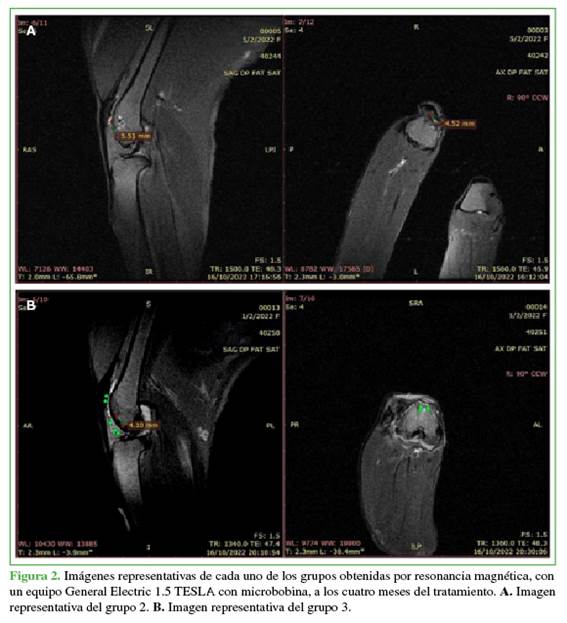

Resultados obtenidos por resonancia magnética

No se visualizaron características regenerativas del cartílago en el grupo 2. Se observó gran cantidad de edema óseo, aumento del derrame articular, sin tejido condral en la zona de la lesión (Tabla).

En el grupo 3, en cambio y según lo comunicado por otros autores,19-21 se observó presencia de cartílago, no había edema óseo, ni derrame articular significativo en la secuencia T1 (Tabla, Figura 2).